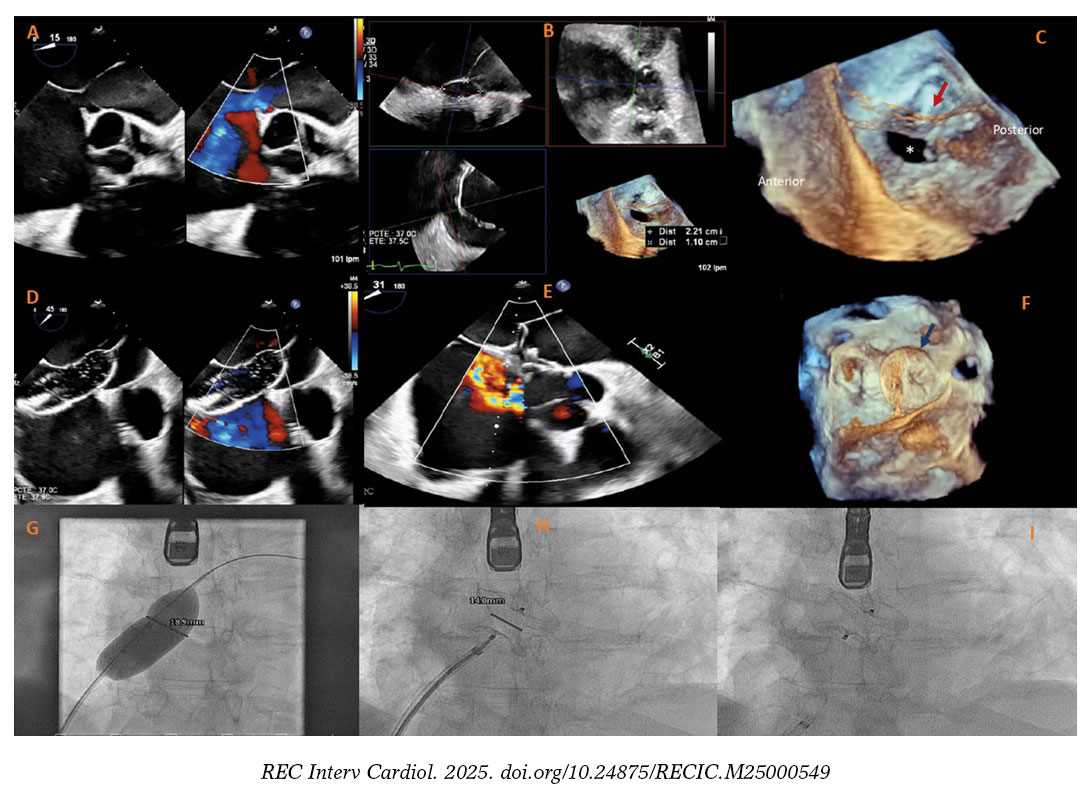

Varón de 67 años con signos de insuficiencia cardiaca derecha secundaria a comunicación interauricular (CIA) con dilatación ventricular derecha, shunt izquierda-derecha significativo (Qp/Qs 1,5) y sin hipertensión pulmonar precapilar significativa (presión arterial pulmonar media, 26 mmHg; resistencia vascular pulmonar, 2 UW). La ecocardiografía transesofágica tridimensional (ETE 3D) reveló la presencia de un cor triatriatum sinister (CTS) con una membrana que se extendía desde el extremo superior y posterior de la fosa oval hasta la cresta pulmonar, con múltiples fenestraciones, la mayor de 24 mm (figura 1A). Se confirmó la presencia de una CIA tipo ostium secundum de 22 × 11 mm, con el borde posterior parcialmente recubierto por la membrana (figura 1B-C). Como el paciente era técnicamente apto y presentaba un riesgo quirúrgico elevado en un contexto de cirrosis, se optó por un abordaje percutáneo. La intervención se realizó bajo guiado simultáneo por ETE 3D y fluoroscopia, la CIA se cruzó con una guía de 0,035 pulgadas y un catéter multipropósito, la medición con balón confirmó la presencia de un defecto de 20 mm y, por último, se implantó con éxito un oclusor septal Amplatzer de 24 mm (Abbott Structural Heart, Estados Unidos) (figura 1D-F). La ETE confirmó la correcta posición del dispositivo, sin shunt residual ni obstrucción del flujo en la aurícula izquierda. Se obtuvo el consentimiento informado del paciente.

Figura 1.

El CTS es una malformación cardiaca poco frecuente que puede coexistir con la CIA tipo ostium secundum en hasta el 33% de los pacientes. Aunque el cierre percutáneo es el método de elección en anatomías favorables, la presencia de CTS puede complicar el despliegue del dispositivo por la definición inadecuada de los márgenes, con el consiguiente mayor riesgo de inestabilidad y embolización del dispositivo. En este caso, el cierre de la CIA fue especialmente complejo, ya que el borde posterior estaba en continuidad directa con la membrana auricular, lo cual planteaba dudas sobre la adecuada aposición del dispositivo. El presente caso pone de manifiesto lo importantes que son las técnicas de imagen avanzada como la ETE 3D en anatomías complejas, ya que permiten una planificación precisa de la intervención y un guiado en tiempo real para garantizar el éxito de la intervención.